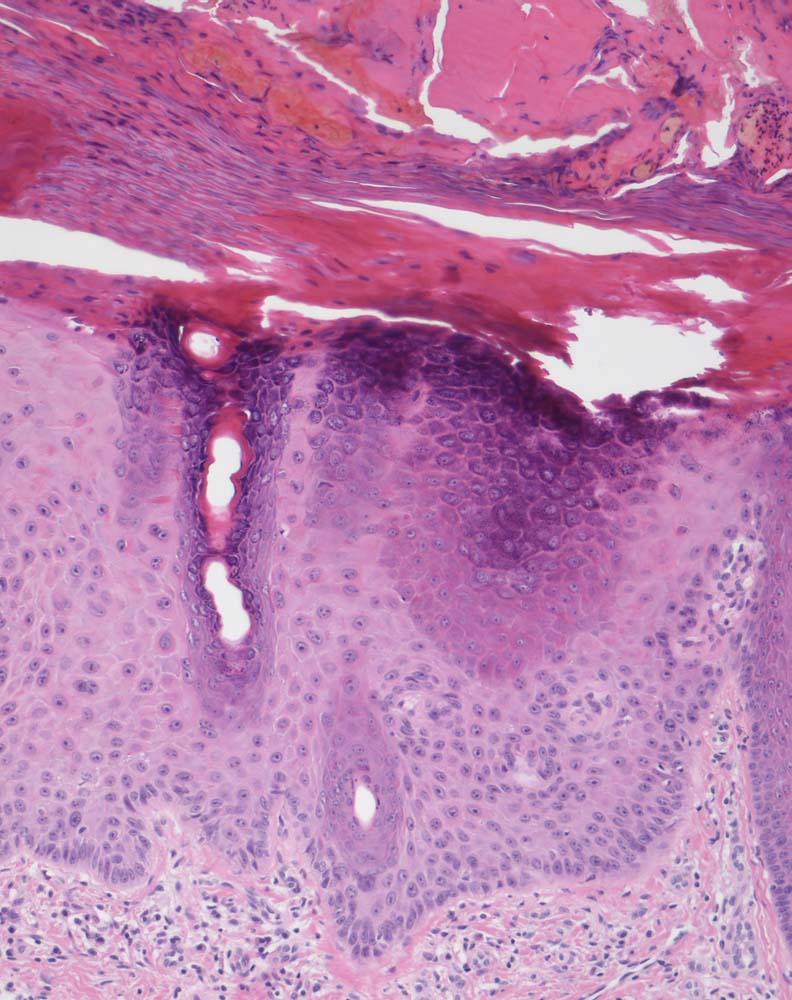

Solare Präkanzerose (Keratose) hyperkeratotischer Typ

Haut, Hand palmar, Finger

Hyper-parakeratotisch verhornende akanthotisch verbreiterte Epidermis mit Serokruste nach mechanischer Irritation. Abblassung und Atypien des Plattenepithels (vergrösserte hyperchromatische Kerne) in den basalen Abschnitten. Die Hautadnexe sind von den dyplastischen Veränderungen ausgespart.

Basalzellkarzinom rechtes Daumensattelgelenk.

Histologie

100